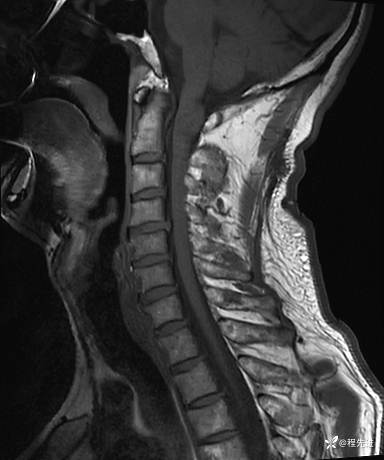

MRI平扫+增强:

T2压脂: